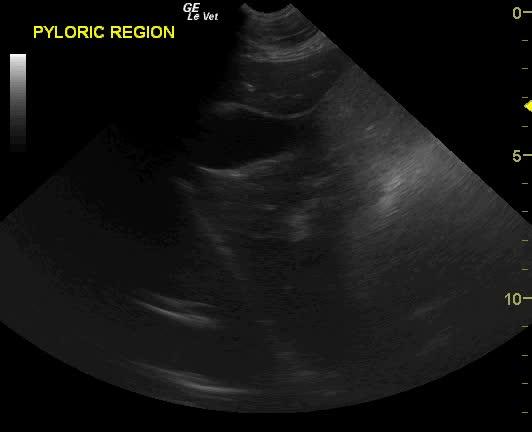

Severe gastric air artifact is noted when imaging the stomach. The normal pylorus is not visible from the right 11-13 intercostal approach suggestive for pyloric displacement. Splenic congestion and splenomegaly is present.